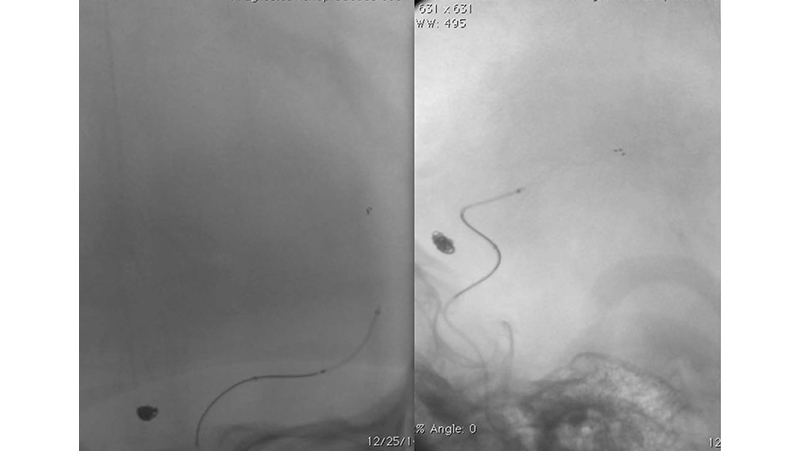

Εικόνα 2: Έγινε εμβολισμός του ανευρύσματος στην οξεία φάση με coils. Στην τελική αγγειογραφία, φαίνεται η πλήρης απόφραξη του ανευρυσματικού σάκκου. Διακρίνουμε όμως και την απόφραξη του Μ1 της αριστεής μέσης εγκεφαλικής αρτηρίας, από θρόμβο που πιθανότατα αποσπάστηκε από την αυχενική έσω καρωτίδα κατά τους χειρισμούς (σημειωτέον ότι η επέμβαση έγινε χωρίς ηπαρίνη επειδή το ανεύρυσμα ήταν ραγέν.